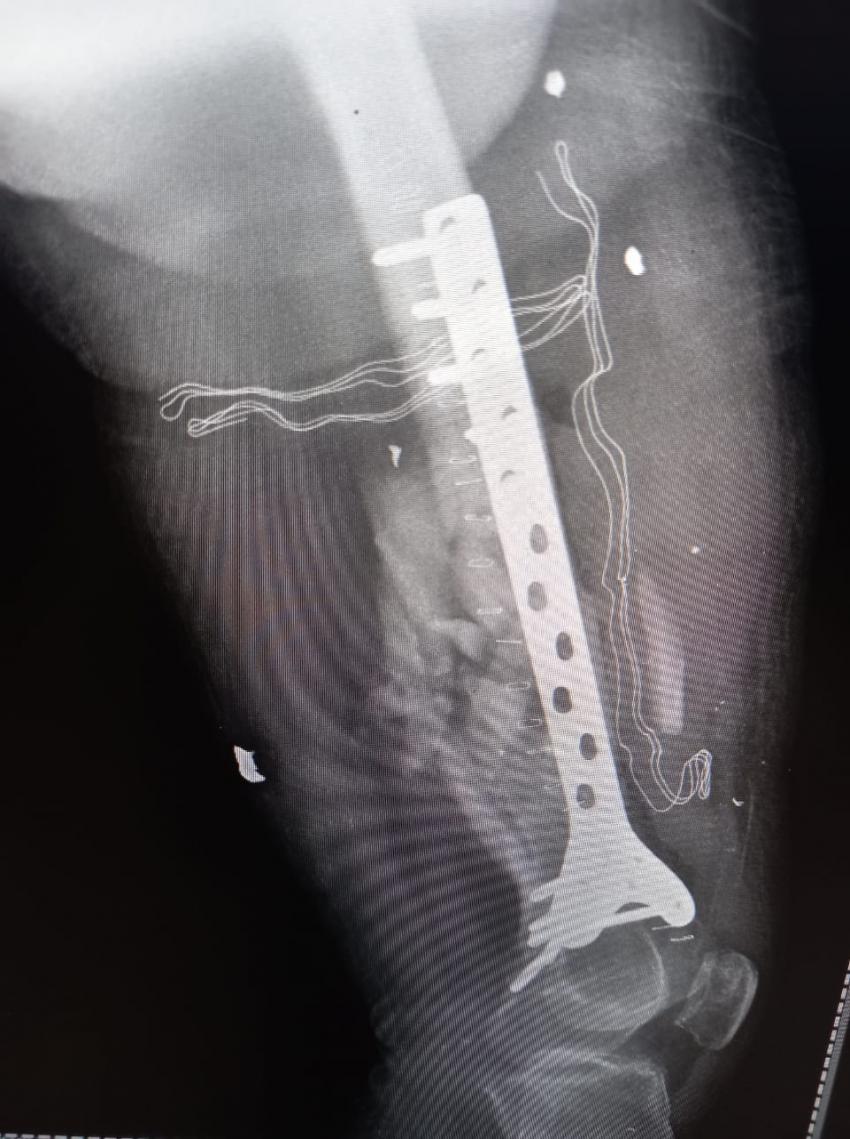

الراي نيوز - في إطار الجهود التي يقدمها المستشفى من أجل تقديم الخدمة والرعاية الطبية والإنسانية للأهل في قطاع غزة، أجرت طواقم المستشفى الميداني الأردني غزة /78 أمس السبت، عملية جراحية لتثبيت كسر مفتوح في أسفل عظم الفخذ (DISTAL FEMUR FX ORIF).

من جانبه بين طبيب جراحة العظام والمفاصل أن المريض كان يعاني من كسر مفتوح في أسفل عظم الفخذ اليمين مما أدى إلى تفتت العظم وتهتك الأنسجة المحيطة به نتيجة الإصابة التي تعرض لها المريض، وتم إجراء عملية جراحية وتركيب صفيحة معدنية وبراغي وإزالة المثبت الخارجي في المستشفى الميداني الأردني لكونه المستشفى الوحيد الذي ما زال مستمراً شمال القطاع.